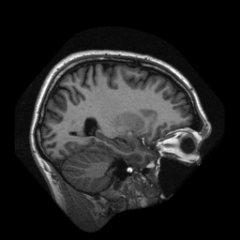

We introduce a neural network framework, utilizing adversarial learning to partition an image into two cuts, with one cut falling into a reference distribution provided by the user. This concept tackles the task of unsupervised anomaly segmentation, which has attracted increasing attention in recent years due to their broad applications in tasks with unlabelled data. This Adversarial-based Selective Cutting network (ASC-Net) bridges the two domains of cluster-based deep learning methods and adversarial-based anomaly/novelty detection algorithms. We evaluate this unsupervised learning model on BraTS brain tumor segmentation, LiTS liver lesion segmentation, and MS-SEG2015 segmentation tasks. Compared to existing methods like the AnoGAN family, our model demonstrates tremendous performance gains in unsupervised anomaly segmentation tasks. Although there is still room to further improve performance compared to supervised learning algorithms, the promising experimental results shed light on building an unsupervised learning algorithm using user-defined knowledge.